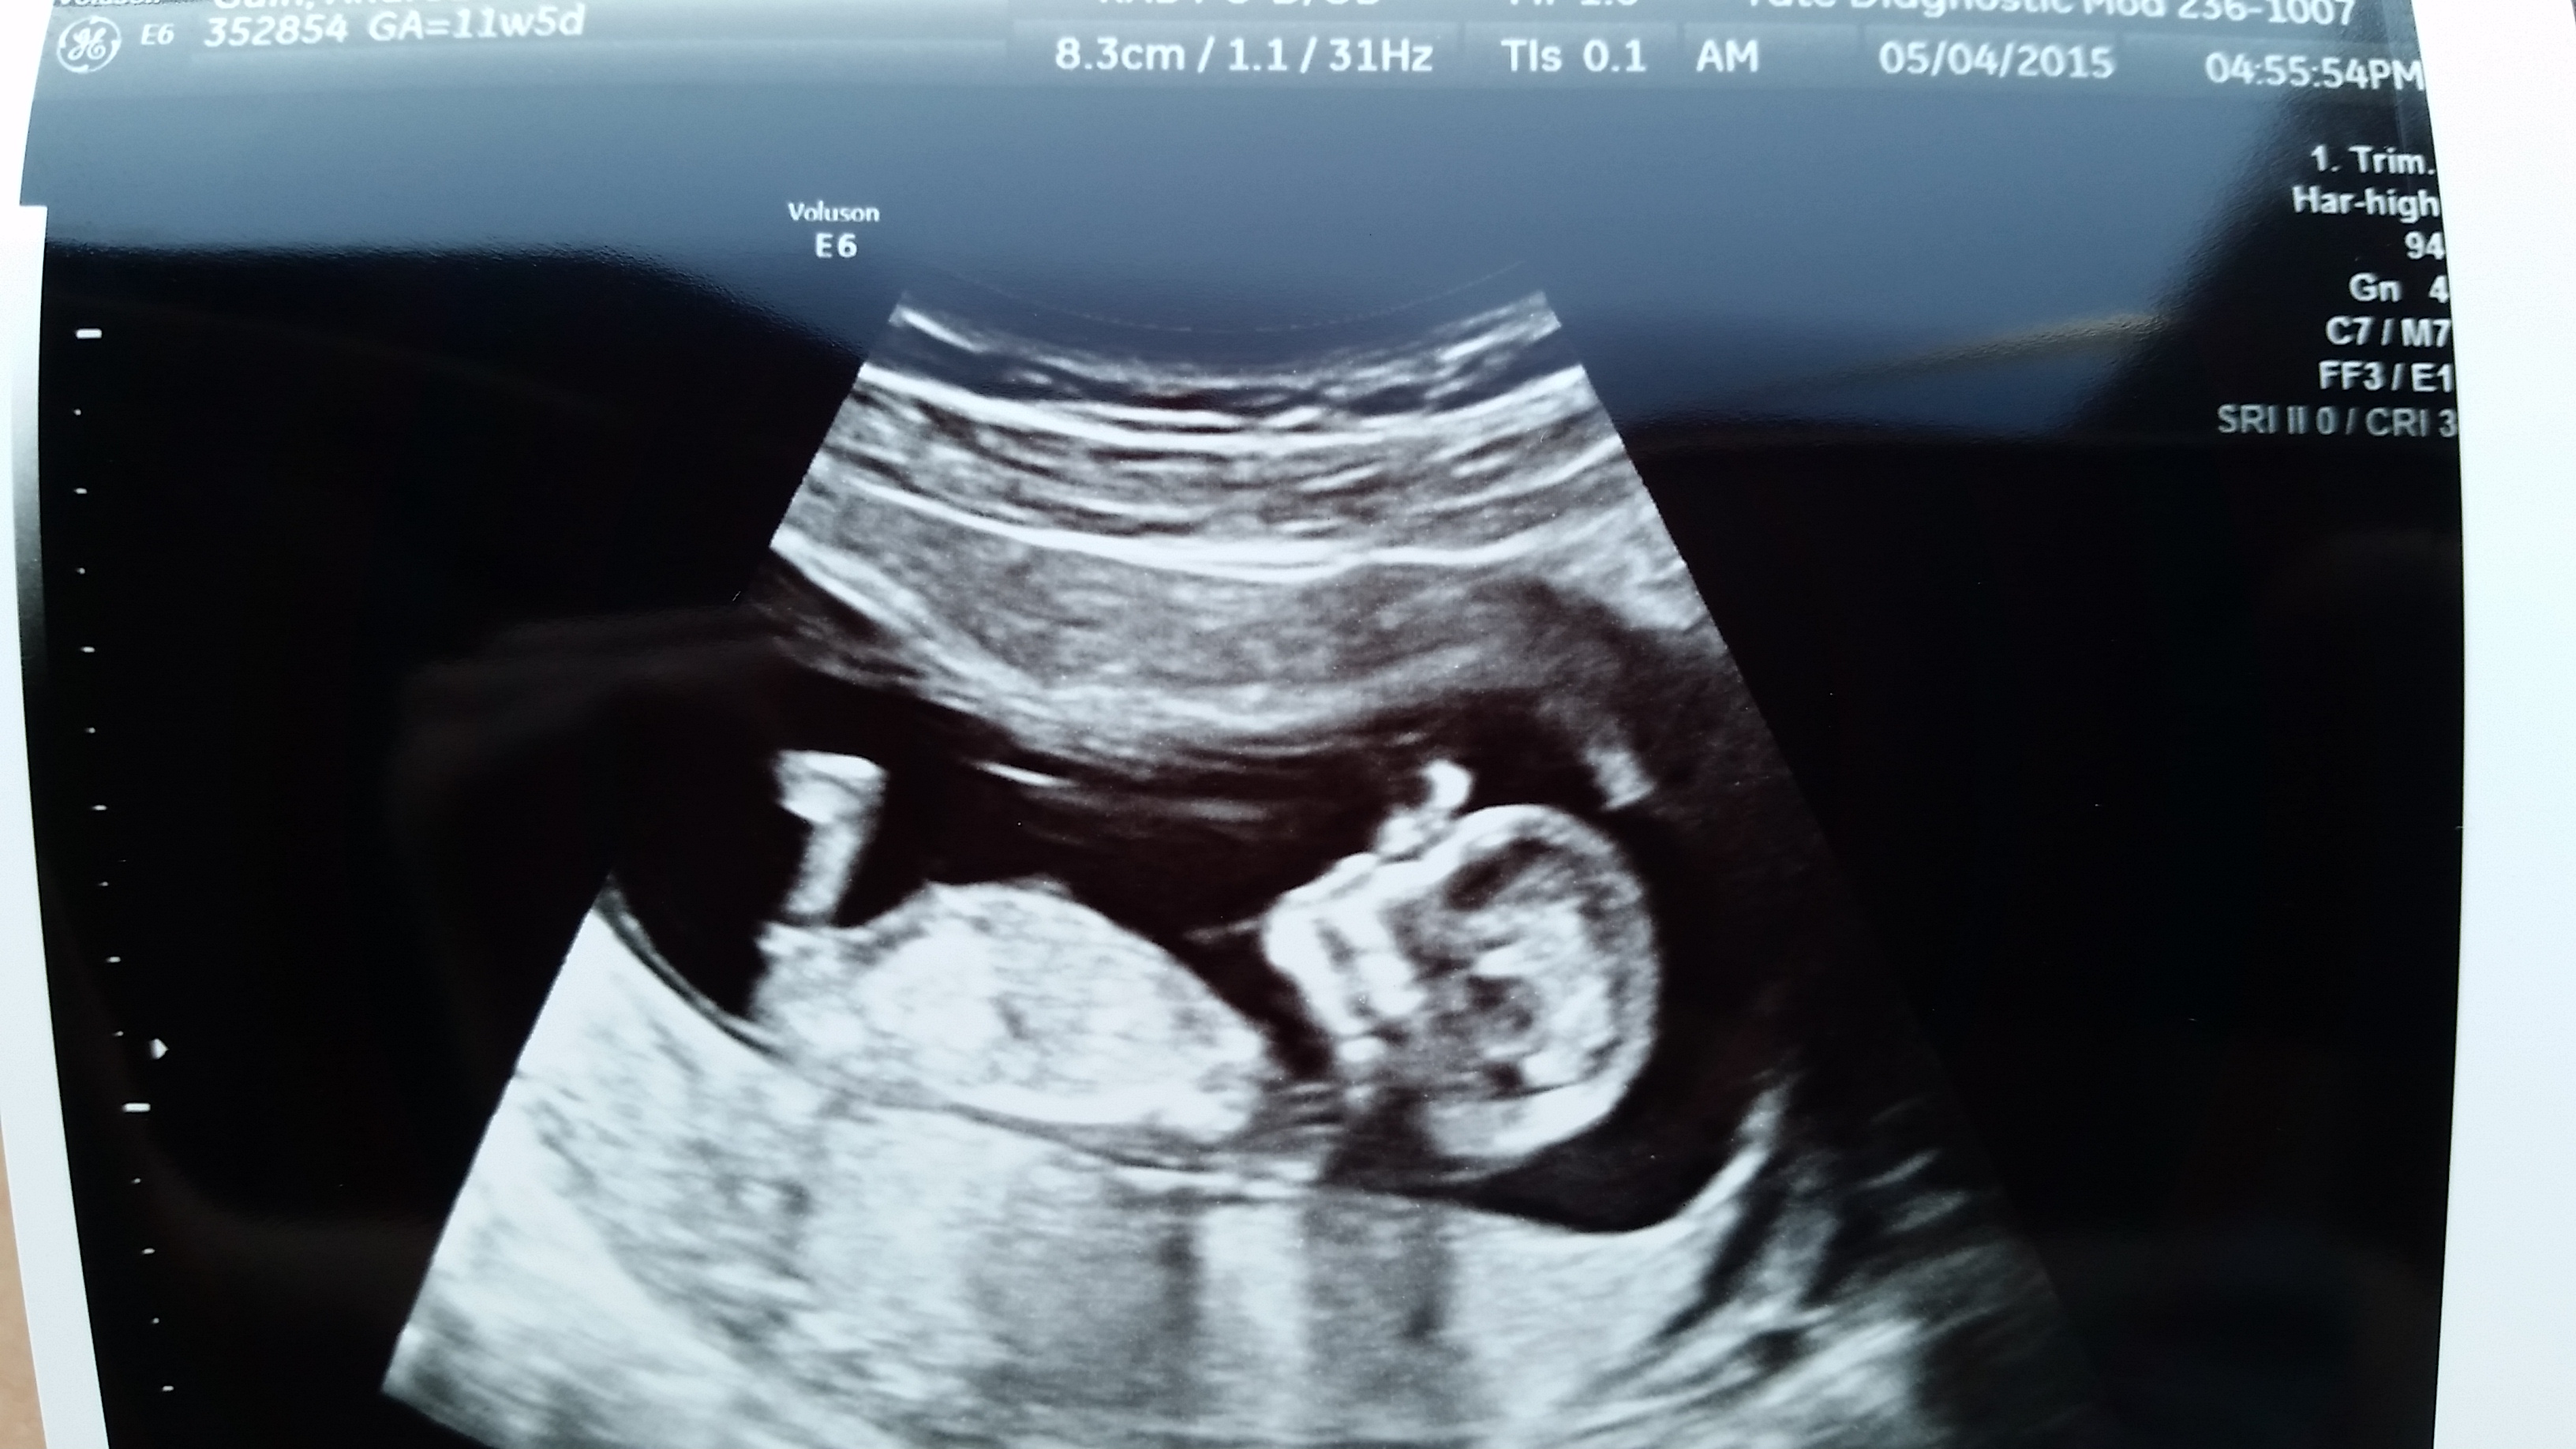

Finally got our first ultrasound. Went in thinking I was 12+4 and it turns out I am actually measuring at 13+6. My due date got pushed up from November 8 to October 30! We have a very squirmy little thumb sucker. So incredible.